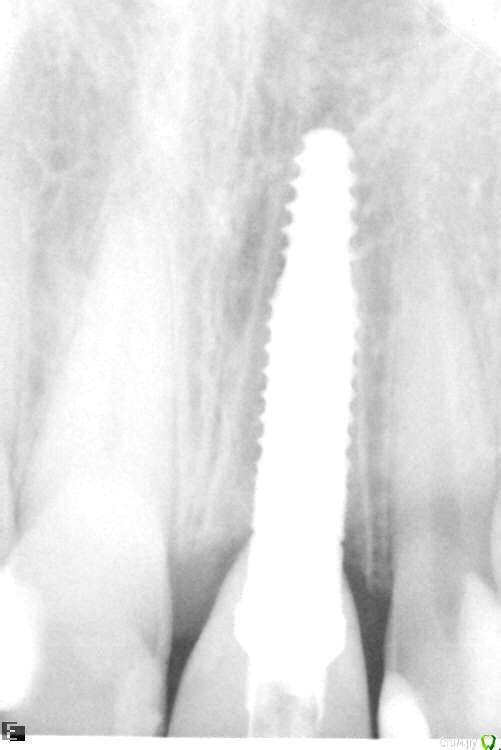

togrul Опубликовано 25 ноября, 2016 Поделиться Опубликовано 25 ноября, 2016 Всем добрый вечер.Сазонова 1.bmpсазонова.bmp 4 Ссылка на комментарий

togrul Опубликовано 25 ноября, 2016 Автор Поделиться Опубликовано 25 ноября, 2016 снимки Ссылка на комментарий

Доктор Добрых Дел Опубликовано 26 ноября, 2016 Поделиться Опубликовано 26 ноября, 2016 Края лунки выглядят как будто в ней граната разорвалась. И согласен с коллегами нужно было ещё заглубить и платформу нёбнее немного. Ссылка на комментарий

togrul Опубликовано 26 ноября, 2016 Автор Поделиться Опубликовано 26 ноября, 2016 (изменено) Края лунки выглядят как будто в ней граната разорвалась. И согласен с коллегами нужно было ещё заглубить и платформу нёбе немного.Спасибо за замечание. При удалении пришлось повозиться. Отлично, надо было заглубить. был графт?Да надо было)Да был Лиопласт. Нужно было Bio oss Изменено 26 ноября, 2016 пользователем togrul Ссылка на комментарий

togrul Опубликовано 28 ноября, 2016 Автор Поделиться Опубликовано 28 ноября, 2016 я толком с семадос не знаком, но у них шестигранник и есть болты с фрезерованной шеей. Топикстартер мог бы лучше пояснить. Добрый день. Семадос шестигранное соединение, как мне объяснили имплантат должен быть поставлен на 3 мм от будущего зенита. Для формирования профиля мягких тканей . 1 Ссылка на комментарий